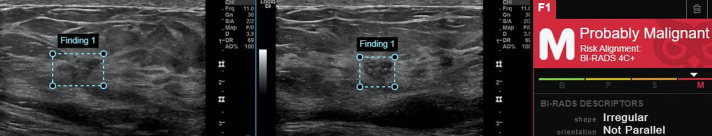

Materials and methods: Seventy suspicious breast mass lesions (53 malignant and 17 benign) from seventy women who underwent diagnostic breast US complemented with shear wave elastography, US-guided core needle biopsy and verified histopathology were enrolled. Two radiologists, one with 15 years of experience and the other with one year of experience, evaluated the images for breast imaging-reporting and data system (BI-RADS) scoring. The less-experienced radiologist re-evaluated the images with the guidance of a commercial AI system and the maximum elasticity from shear wave elastography. The BI-RADS scorings were processed to determine diagnostic performance and malignancy detections.

Results: The experienced reader demonstrated superior performance with an area under the curve (AUC) of 0.888 [95% confidence interval (CI): 0.793-0.983], indicating high diagnostic accuracy. In contrast, the Koios decision support (DS) system achieved an AUC of 0.693 (95% CI: 0.562-0.824). The less-experienced reader, guided by both Koios and elasticity, showed an AUC of 0.679 (95% CI: 0.534-0.823), while Koios alone resulted in an AUC of 0.655 (95% CI: 0.512-0.799). Without any guidance, the less-experienced reader exhibited the lowest performance, with an AUC of 0.512 (95% CI: 0.352-0.672). The experienced reader had a sensitivity of 98.1%, specificity of 58.8%, positive predictive value of 88.1%, negative predictive value of 90.9%, and overall accuracy of 88.6%. The Koios DS showed a sensitivity of 92.5%, specificity of 35.3%, and an accuracy of 78.6%. The less-experienced reader, when guided by both Koios and elasticity, achieved a sensitivity of 92.5%, specificity of 23.5%, and an accuracy of 75.7%. When guided by Koios alone, the less-experienced reader had a sensitivity of 90.6%, specificity of 17.6%, and an accuracy of 72.9%. Lastly, the less-experienced reader without any guidance showed a sensitivity of 84.9%, specificity of 17.6%, and an accuracy of 68.6%.

Conclusion: Diagnostic evaluation of the suspicious masses on breast US images largely depends on experience, with experienced readers showing good performances. AI-based guidance can help improve lower performances, and using the elasticity metric may further improve the performances of less experienced readers. This type of guidance may reduce unnecessary biopsies by increasing the detection rate for malignant lesions and deliver significant benefits for routine clinical practice in underserved areas where experienced readers may not be available.